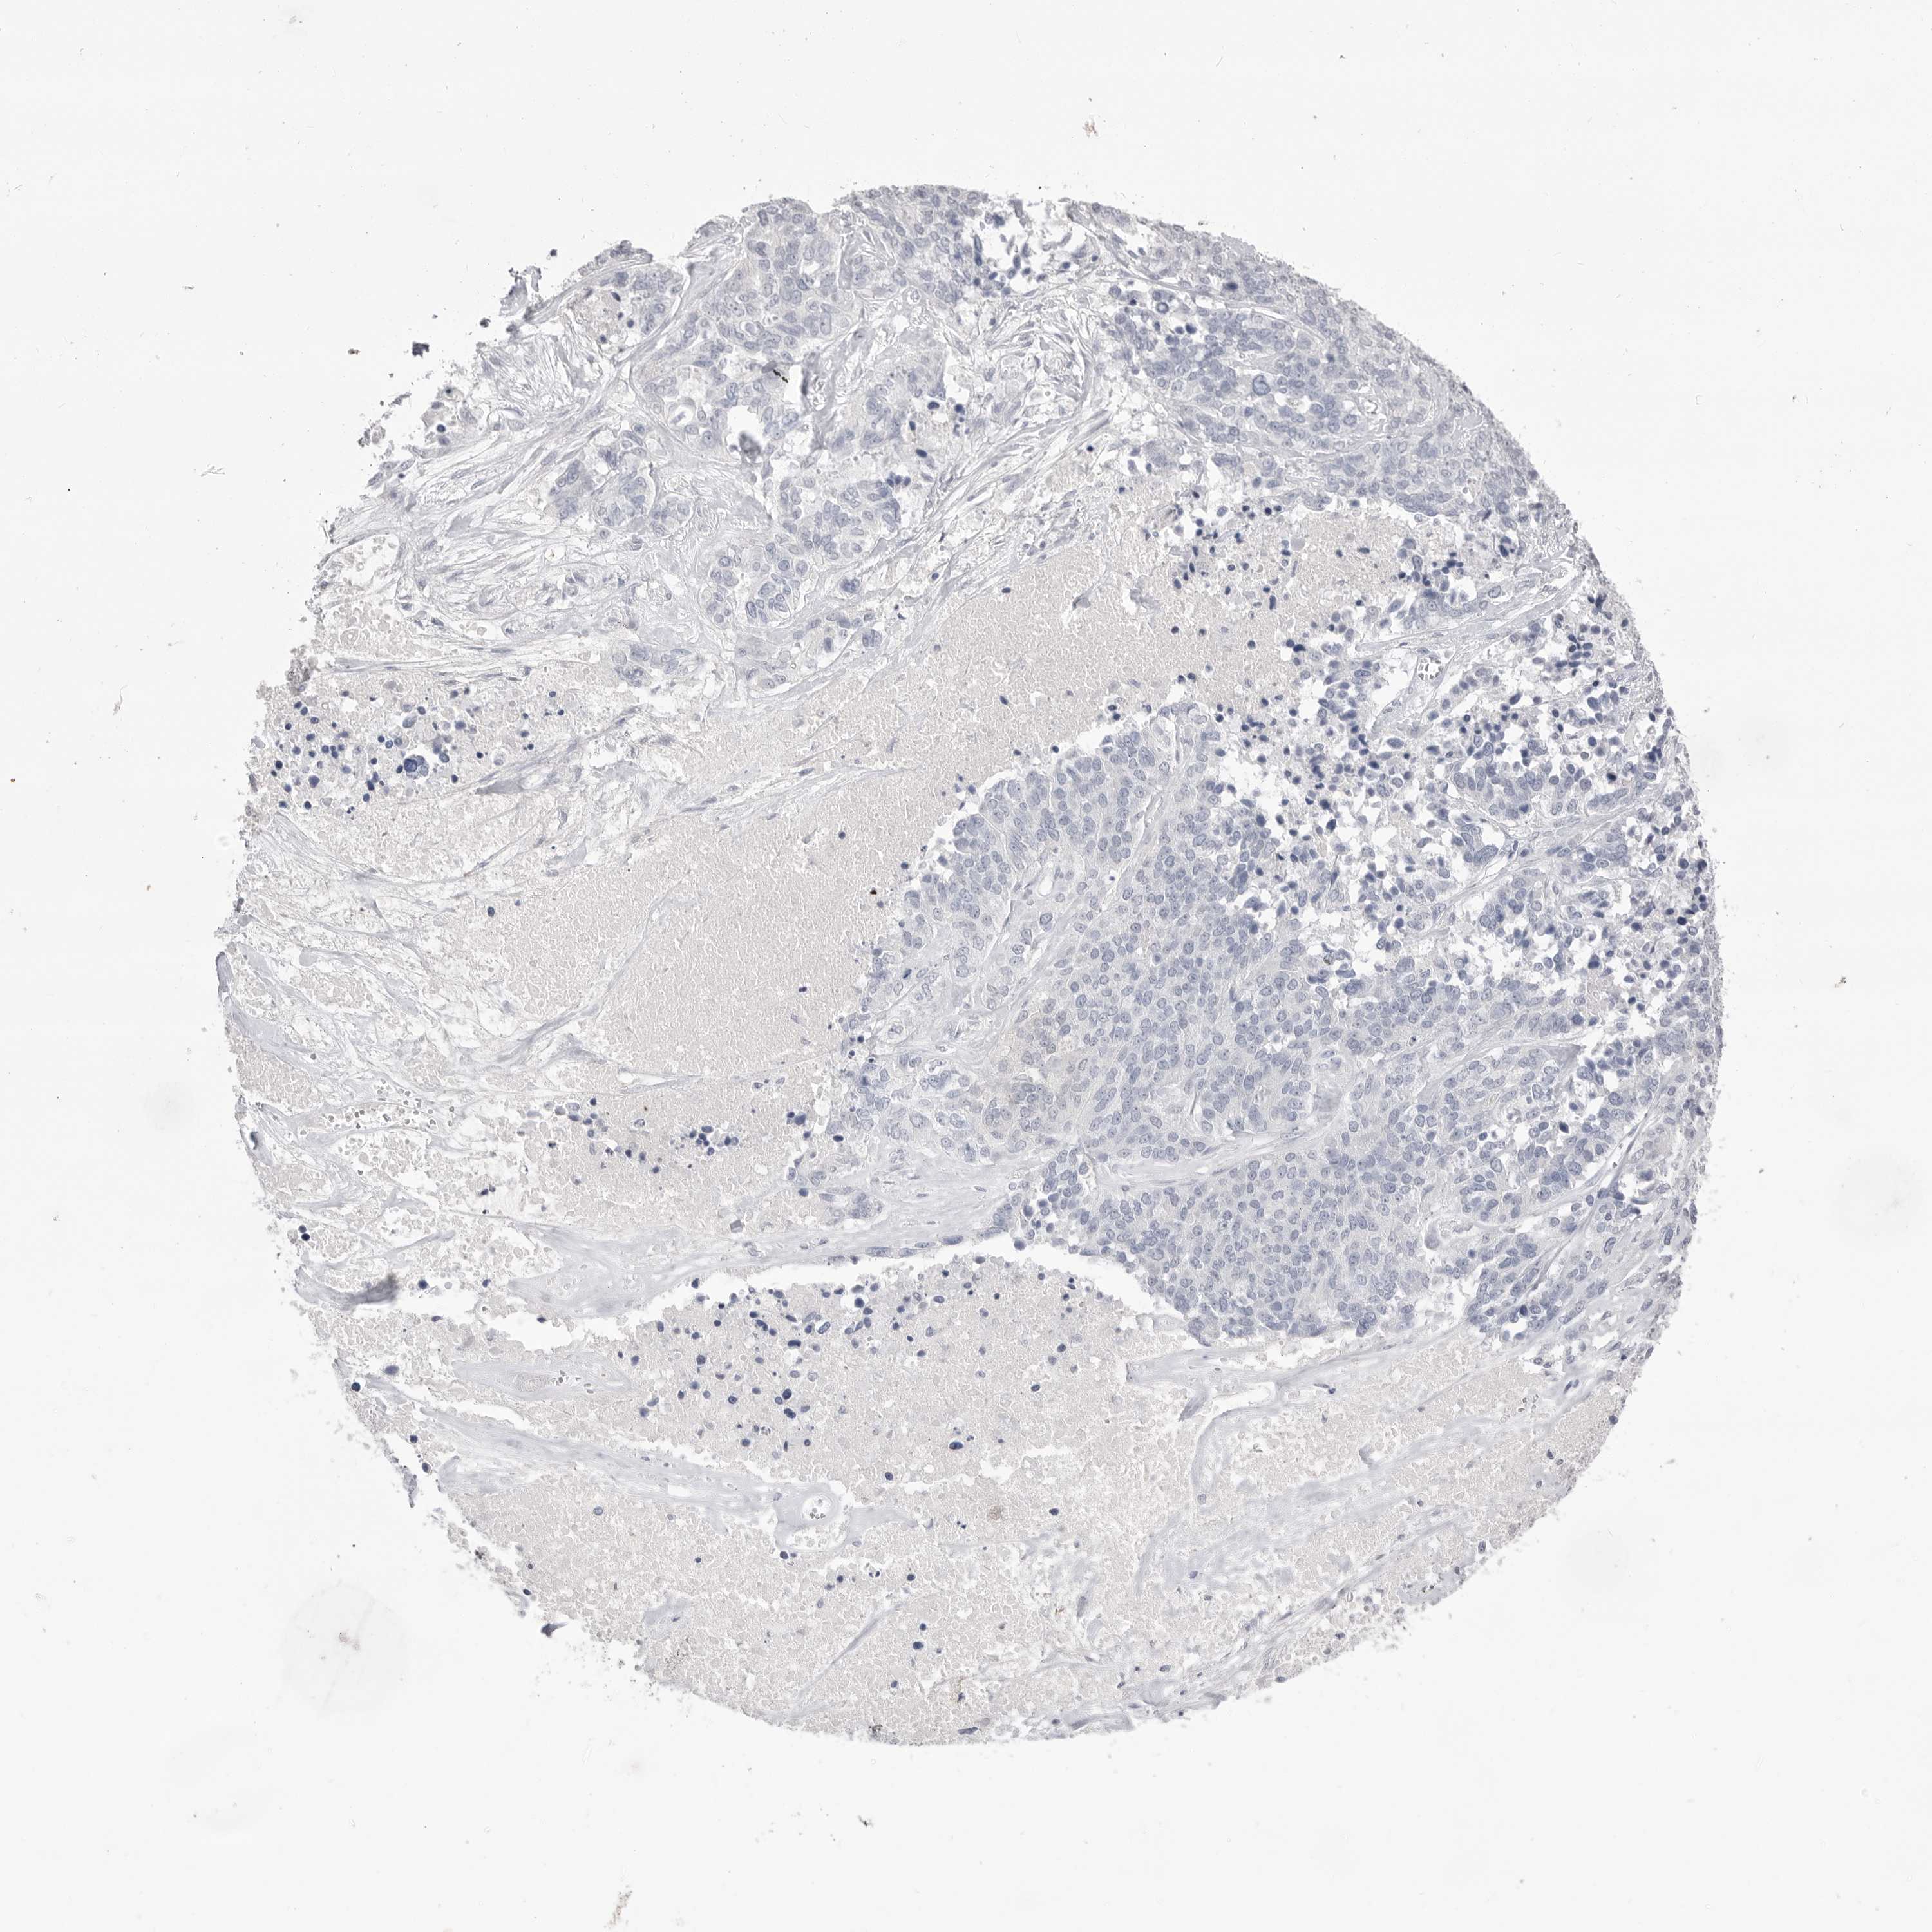

OVARIAN CANCER - Protein expressioni

A mouse-over function shows sample information and annotation data. Click on an image to view it in a full screen mode. Samples can be filtered based on level of antibody staining by selecting one or several of the following categories: high, medium, low and not detected. The assay and annotation is described here.

Note that samples used for immunohistochemistry by the Human Protein Atlas do not correspond to samples in the TCGA dataset.

Antibody stainingi

Antibody staining in the annotated cell types in the current human tissue is reported as not detected, low, medium, or high, based on conventional immunohistochemistry profiling in selected tissues. This score is based on the combination of the staining intensity and fraction of stained cells.

Each image is clickable and will lead to virtual microscopy that enables deeper exploration of all samples and also displays staining intensity scores, fraction scores and subcellular localization as well as patient and tissue information for each sample.

Antibody HPA046340